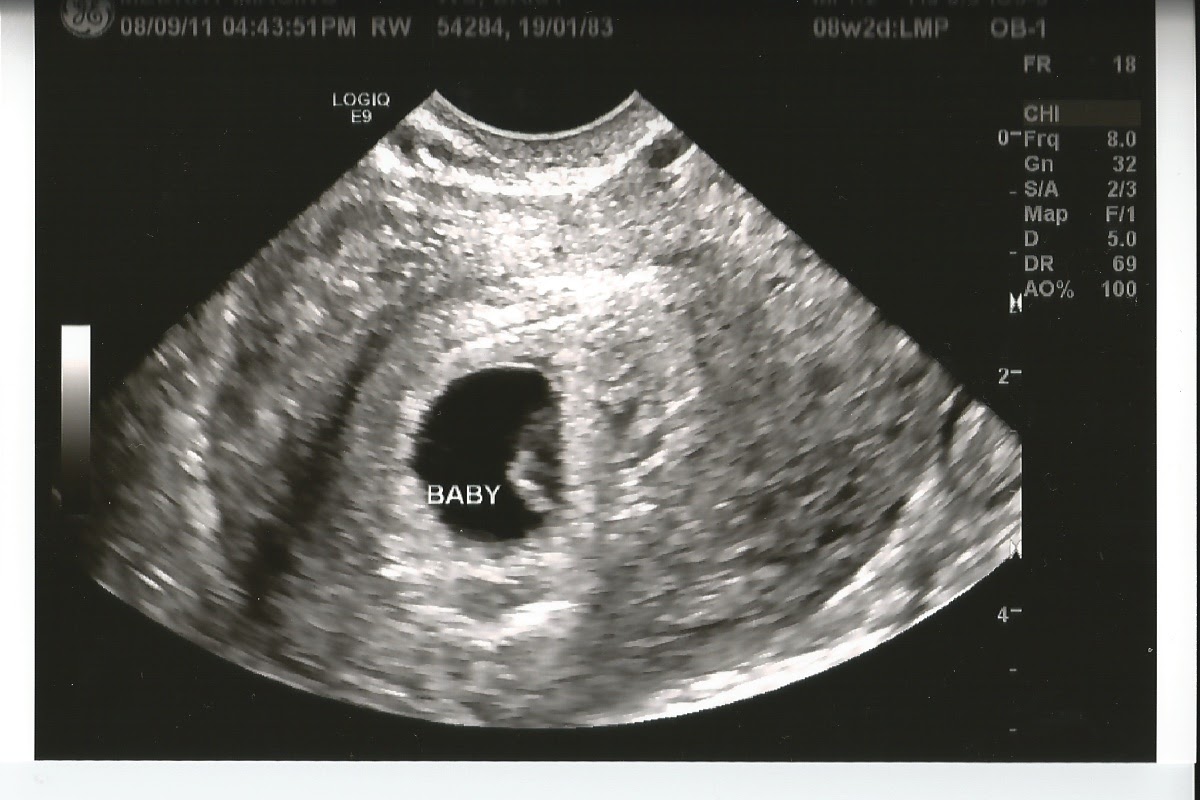

แชร์ประสบการณ์อัลตร้าซาวน์ครั้งแรก

อันนี้เป็นท้องแรก หลังจากใช้ที่ตรวจ ตรวจการตั้งครรภ์เอง ปรากฎว่าขึ้น 2 ขึด ดีใจฝุดๆ จากนั้นไม่รอช้ารีบไปตรวจซ้ำอีกทีที่โรงพยาบาลเลยจ้า ไปถึงก็รอคิวเข้าพบคุณหมอ ระหว่างรอตื่นเต้นพอสมควร ยังไม่รู้ว่าจะได้ซาวน์ด้วย พอเข้าไปที่ห้องคุณหมอก็ถามว่าประจำเดือนมาครั้งสุดท้ายเมื่อไหร่…